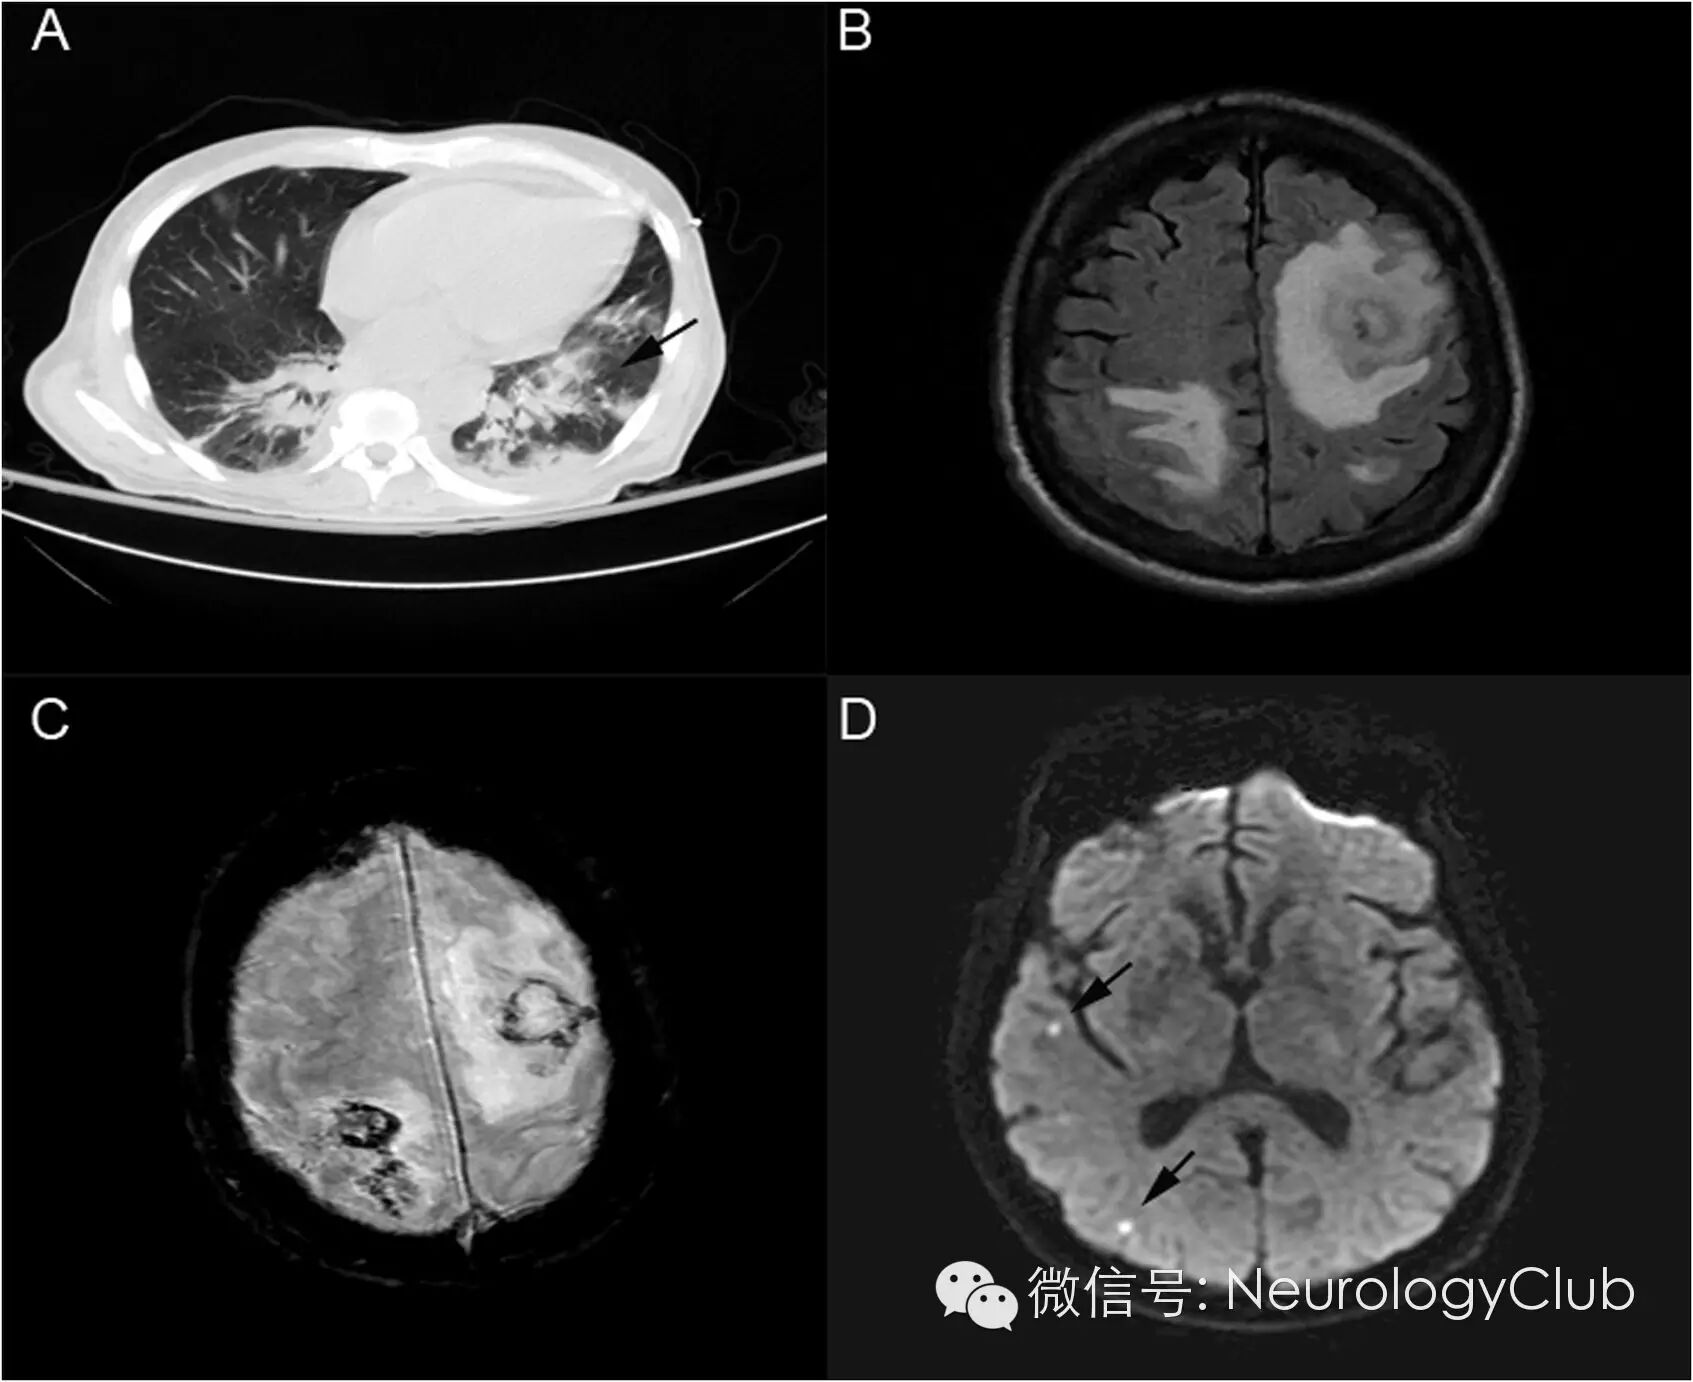

70岁男性,既往诊断为慢性淋巴细胞白血病,查白细胞计数T辅助细胞95.3/mm3,分类淋巴细胞100%,但患者拒绝治疗。患者后出现排痰性咳嗽和进行性加重的意识障碍。入院时,出现感染性休克。胸部CT提示两肺渗出性病变。头颅MRI提示出血伴周围水肿以及多发小梗死灶(图1)。左侧额叶病灶活检提示脓肿伴大片坏死,中性粒细胞炎症,可见有隔膜的真菌菌丝及锐角分支(图2 )。

(图1:A:胸部CT提示肺下叶渗出性病变;B-C:FLAIR和T2梯度回波序列提示出血伴周围水肿;D:DWI提示多发弥散受限病灶,不符合特殊血管分布)

影像学上,侵袭血管的中枢神经系统曲霉菌病表现为多灶出血病变伴弥散受限。出血倾向的原因是因为曲霉菌产生的弹性蛋白酶可降解动脉内弹性膜,而血栓形成和梗死的出现是由于真菌阻塞穿支动脉管腔。本例患者的头颅MRI表现比较典型,可见出血伴外周水肿,同时存在小的不符合特殊血管分布的多发弥散受限病灶。真菌可越过血管壁传播,导致邻近脑组织脓肿形成。